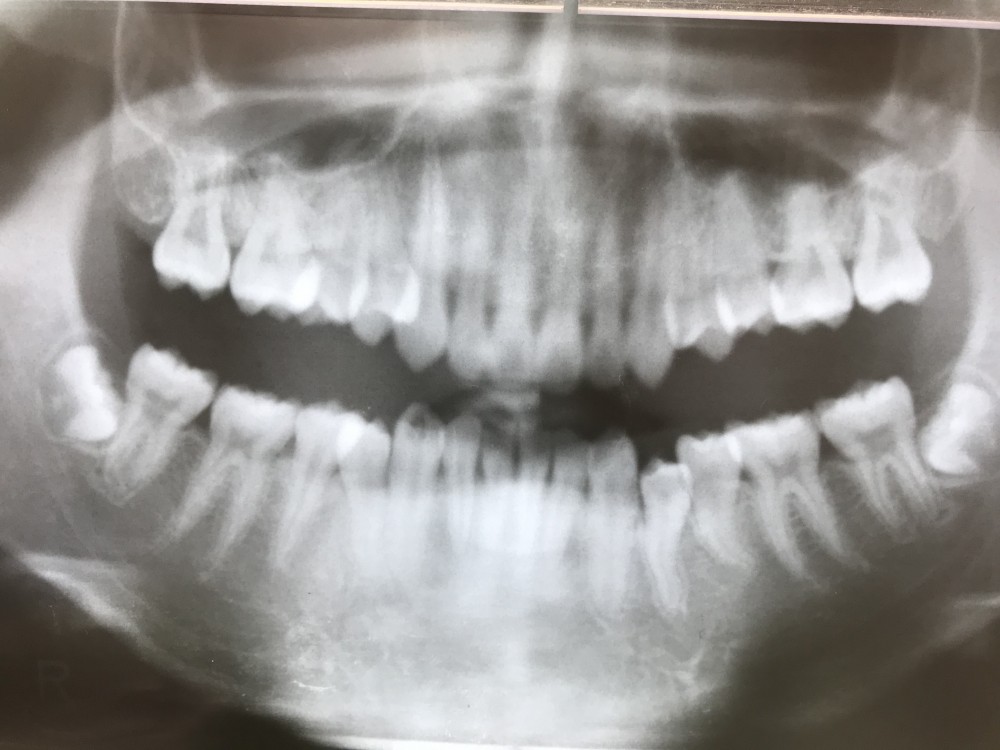

下の写真は、初診時から2年3ヶ月後のもの。

15才3ヶ月です。

左下4に関しては、今のところご希望ないために経過観察中です。